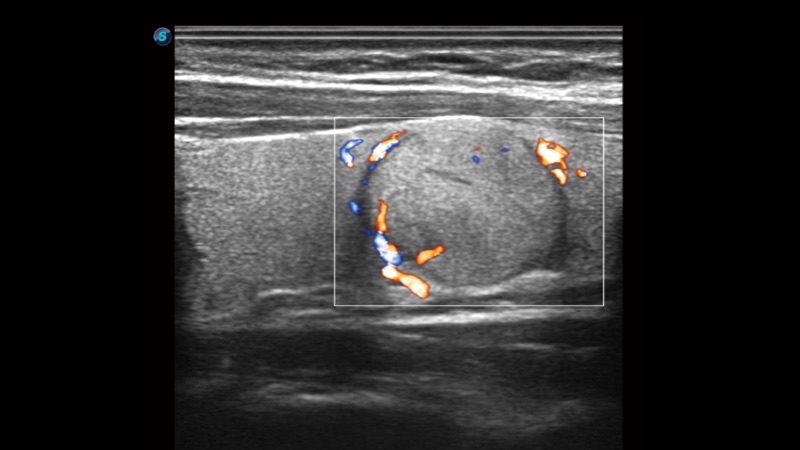

SR Flow高分辨率血流成像

高分辨率血流成像技术提高了对低速血流信号的检测能力。在提高空间分辨率的同时,也克服了血流外溢现象,为用户提供更加真实的血流动力学信息。